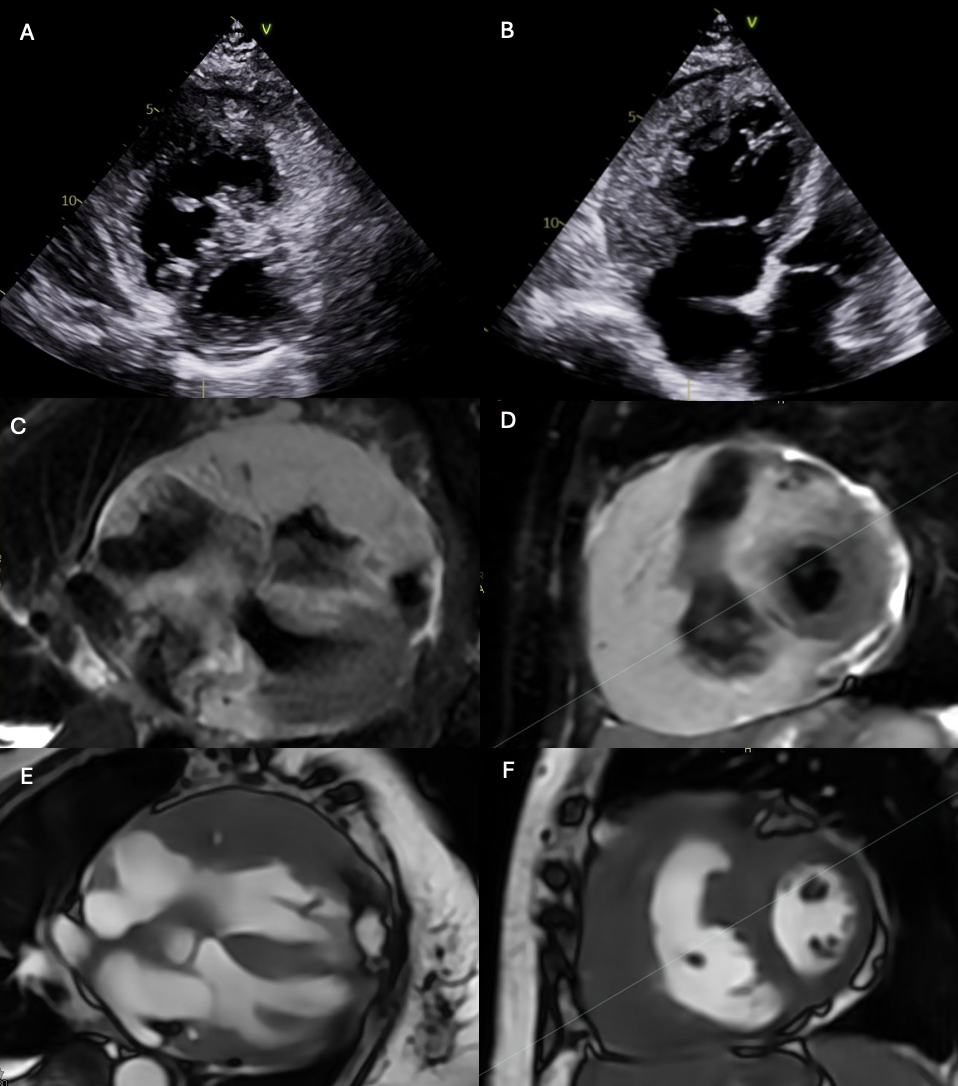

A 78-year-old female with hypertension and chronic kidney disease was discharged from an outside hospital after a diagnostic and therapeutic pericardiocentesis with cytology indicating B-cell lymphoma. Prior to outpatient follow up, she presented with worsening dyspnea. She was hemodynamically stable. Hs troponin T was 949 ng/L and pro-BTNP 12,015 pg/mL. EKG - sinus rhythm with 1st degree AV block. Transthoracic echocardiogram (TTE) revealed a small pericardial effusion and a large mass that infiltrated the free wall of the right ventricle (RV) (figure 1). RV systolic function was severely reduced with RV free wall strain (RVFWS) -0.4%.

Cardiac MRI (CMRI) showed thickening and edema consistent with extensive infiltration from B-cell lymphoma of the RV free wall, RA, basal anteroseptum of the LV, and circumferentially in the atrioventricular groove (figure 1). Quantitative LVEF was 48% with focal hypokinesis of the basal septum. RVEF was 32% with akinesis of most of the RV free wall.

Bone marrow biopsy confirmed diffuse large B-cell lymphoma. She was initiated on DA-EPOCH-R in the CCU without complication. Serial TTE showed rapid regression of lymphoma after 1 cycle with normalization of RV function RVFWS -22.3%.

In our patient, extensive infiltration of the RV free wall resulted in heart failure. TTE with RV strain identified RV dysfunction secondary to tumor infiltration and subsequent rapid improvement following initiation of chemotherapy. CMRI was useful to fully characterize the location and extent of cardiac infiltration.